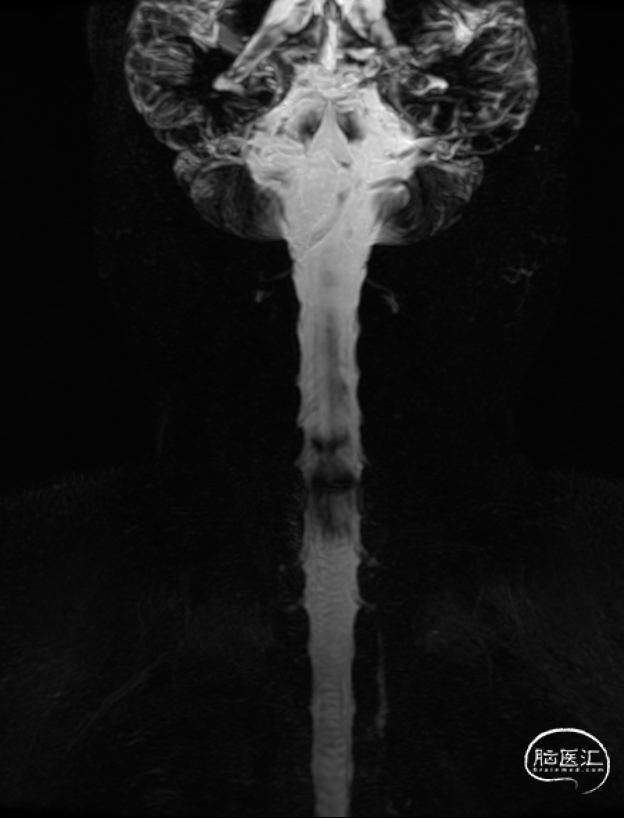

患者因“自发性双侧亚急性硬膜下血肿”收入功能神经外科,我科经过仔细全面检查,考虑诊断为“自发性低颅压头痛”并经MRI全脊柱水成像确定原因为寰枢椎之间有一处硬膜窦道,遂采用了精准微创的方法行C臂定位下硬脑膜漏口硬膜外血贴治疗术。术前患者一直卧床半月,术后第二天患者既症状明显改善下床活动,后患者治愈出院,未遗留神经并发症。2周后经MRI复查漏口已消失。本案例详细资料于2018.3.25日发表于《神外资讯》的 颅脑创伤-神经重症病例周刊(第59期)。

图7:2周后脊髓MRI水成像复查瘘口消失。